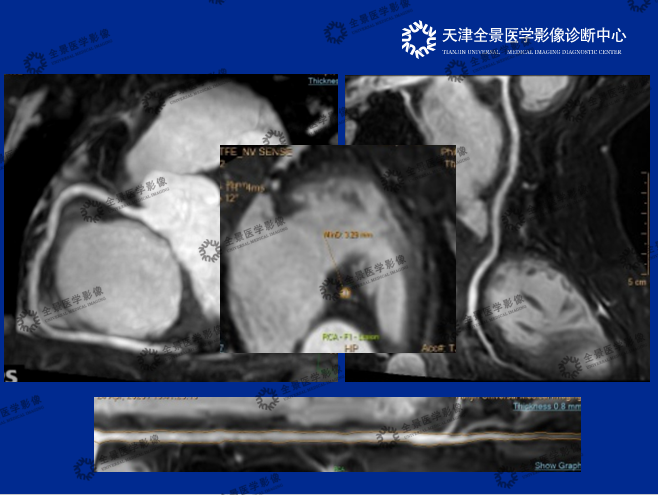

介绍了心脏磁共振的检查原理,分享了丰富案例,总结了CMRA的优势,即无创、避免碘对比剂过敏、无辐射,特别是弥补了冠脉严重钙化,CTA无法评估管腔狭窄程度的局限性。

2.《3.0T磁共振冠状动脉成像》 汇报人:宫健

详细介绍了无对比剂心脏磁共振(CMR)与对比剂心脏磁共振(CMRA)的成像对比,展现了任意层面成像的优势。